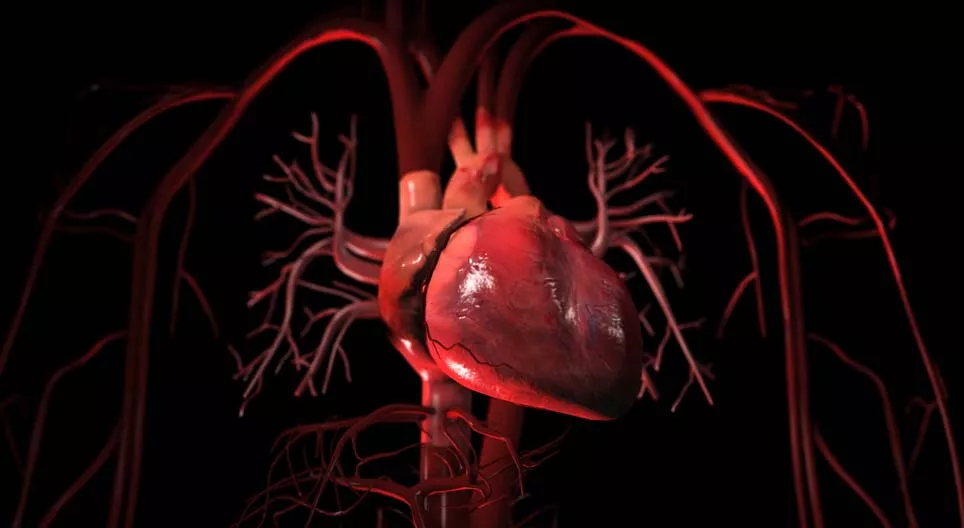

A vérkeringés

A vérünk folyamatos áramlása, keringése a vérkeringési rendszerünkben történik.